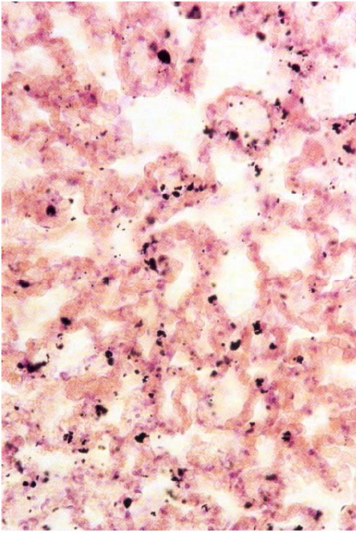

What is the fate of an alveolar macrophage?